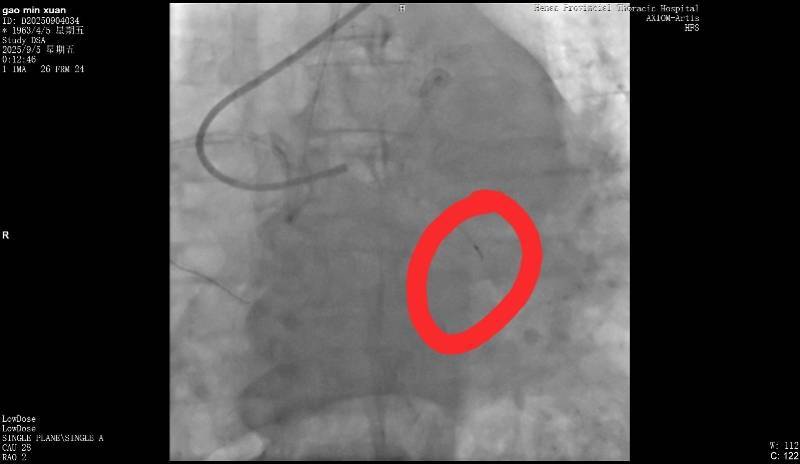

断裂的导丝。受访者供图

9月5日,高女士父亲在该医院做冠脉造影,手术进行了近3个小时。高女士回忆说,手术结束后,负责手术的医生告诉她,“在微创探查体内的时候,一截导丝断裂。”当高女士询问能否再次实施手术取出时,医生表示因病患年纪较大,开胸手术存在危险,并没有取出的必要。但对于遗留导丝会否在后续造成长期影响,该医生则称“无法确定”。

高女士提供的病程记录显示,“手术操作过程中出现回撤导丝困难,送入微导管尝试至坎顿处未成功,退出微导管时远段导丝断裂,多途径尝试取出断裂导丝均未能成功。”资料还指出,“通过复查造影,回旋支近段残余狭窄小于30%,未见明显夹层、无复流。”

南都记者留意到,该病程记录给出了心血管外科一病区会诊意见,称“回旋支内见离断的介入导丝,外科取出导丝意义不大,建议内科治疗”。